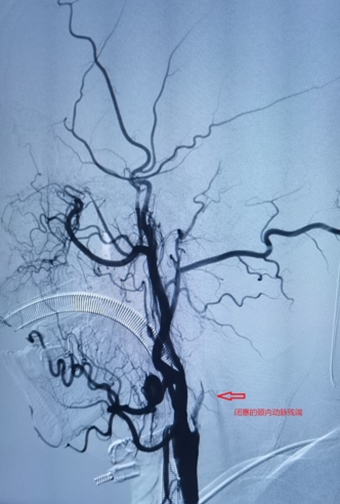

1、左侧颈内动脉末端闭塞,急诊导管抽栓+支架拉栓1例;

0009.jpg

0010.jpg

0011.jpg

0012.jpg